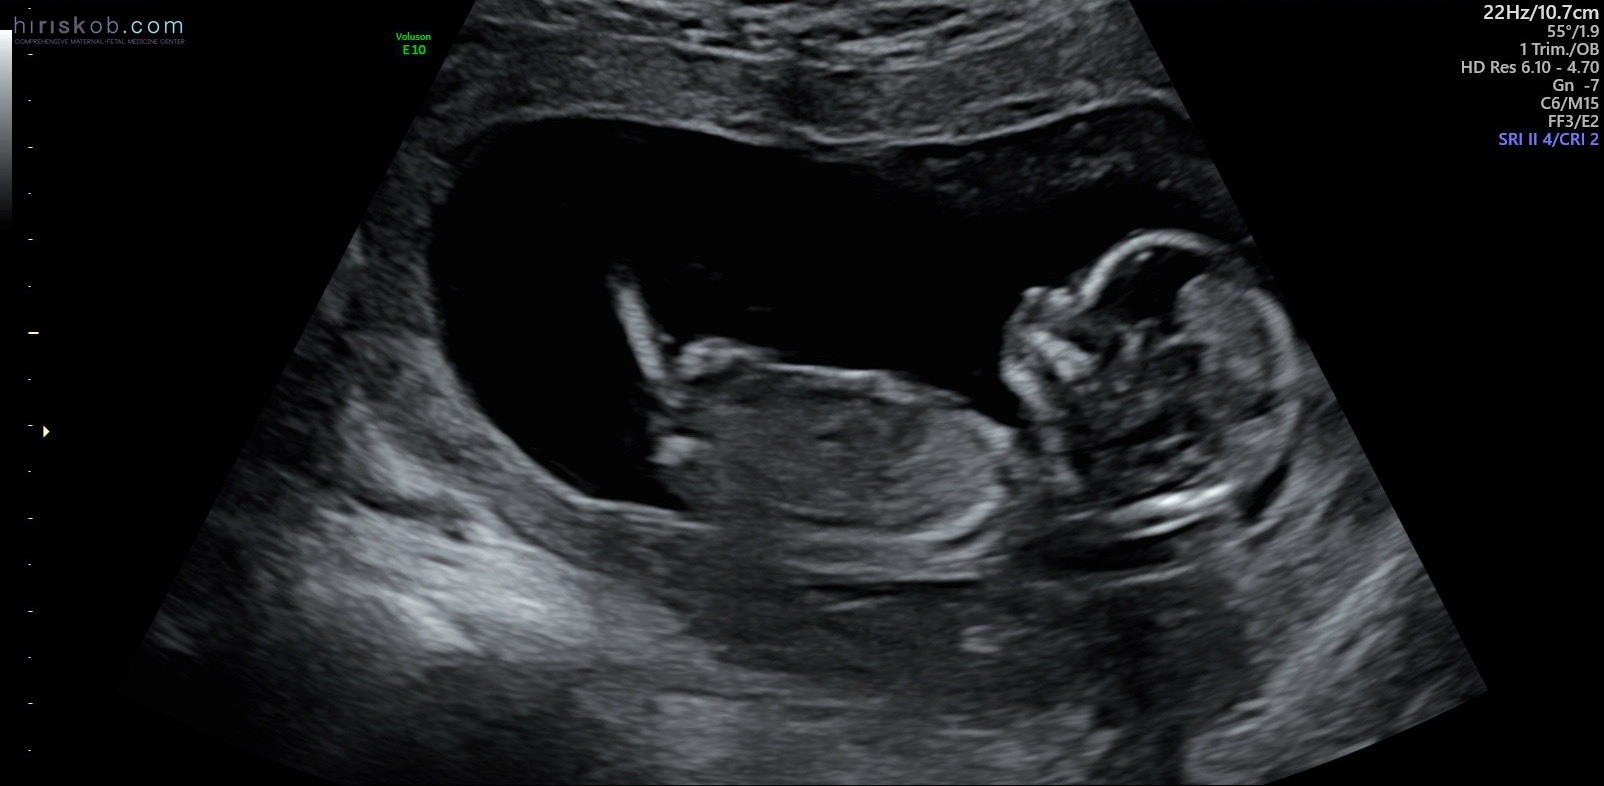

I saw the “normal OB” at 13 weeks. We did all the first trimester genetic testing (called NIPT testing) — everything came back normal. A high-risk OB did a 30-minute ultrasound with me where she painstakingly took every single measurement possible. That was also completely normal.

Baby girl at 14 weeks.